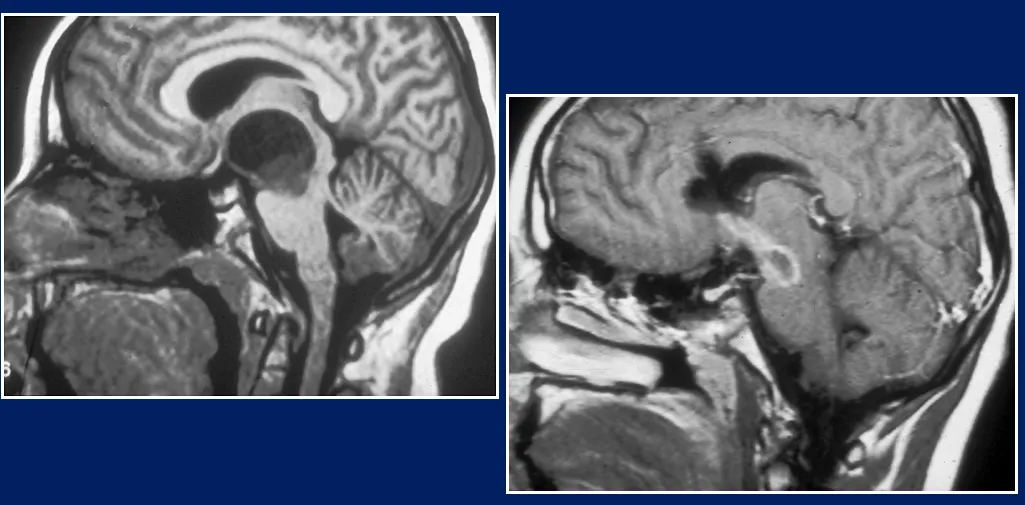

▼患者术前影像图片

正如在这里看到的,肿瘤长得很大,但动脉没有受压,神经被挤到了外围。所以我说可以做手术。可以看到视神经,颅神经。

▼患者术后影像图片

这是一个孩子被医院放弃的案例。他们说"没办法,回家吧"。他们来找我们了。我说"也许我们可以切除这些肿瘤"。

因此,我们采用了经胼胝体+经胼胝体+经脑室入路,我们确实能够完全切除肿瘤。